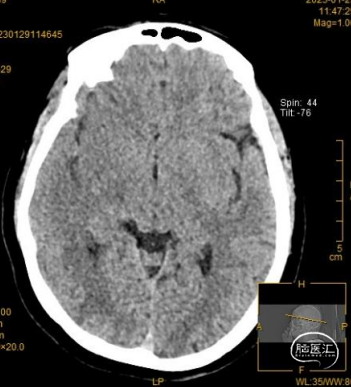

溶栓前颅脑CT提示考虑右侧大脑中动脉致密征,支持大脑中动脉为责任病变。

溶栓后颅脑CT见右侧大脑中动脉远端致密征,右外侧裂池变窄,同并见“岛带征”,考虑右侧急性脑梗塞,必要时进一步MR检查和/或CT脑灌注成像。